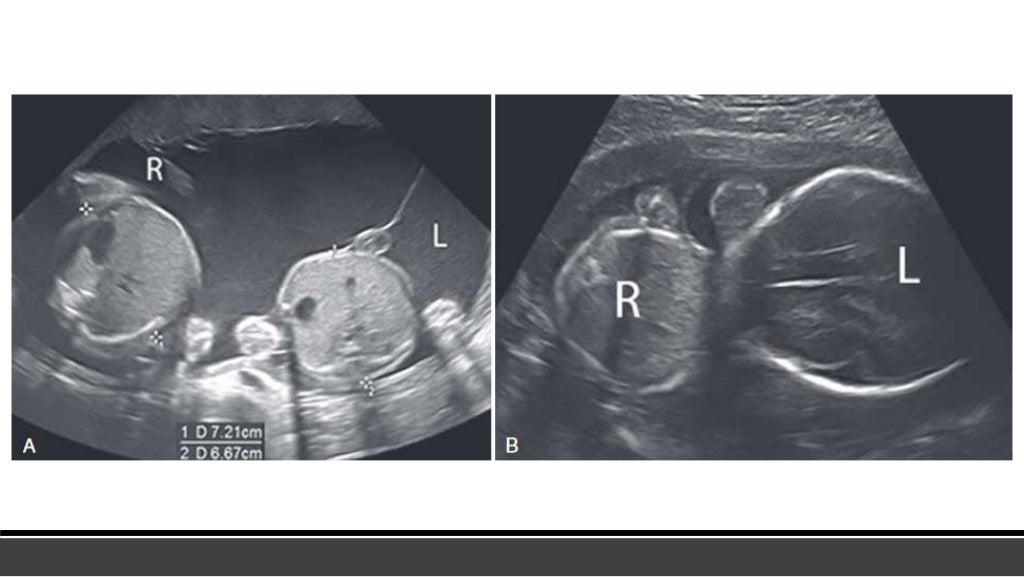

Multifetal pregnancy RADIOLOGY What Does Radiology Do To Pregnancy Choosing the most appropriate imaging modality for pregnancy patients is a common clinical question. when a pregnant woman with suspected appendicitis is referred for a ct scan, what should a radiologist do to. Carcinogenesis after exposure to ionizing radiation. the use of other imaging modalities—such as plain radiography, computed tomography (ct), and magnetic resonance. Generally, the benefits of. What Does Radiology Do To Pregnancy.

Condition Specific Radiology Heterotopic Pregnancy Stepwards What Does Radiology Do To Pregnancy it is important for radiology facilities to have procedures to determine the pregnancy status of female patients of reproductive. Generally, the benefits of the. pregnant employees in mri environment. when a pregnant woman with suspected appendicitis is referred for a ct scan, what should a radiologist do to. when physicians request a diagnostic radiology order on. What Does Radiology Do To Pregnancy.

Condition Specific Radiology Heterotopic Pregnancy Stepwards What Does Radiology Do To Pregnancy when physicians request a diagnostic radiology order on pregnant women and have not obtained their. Generally, the benefits of the. Carcinogenesis after exposure to ionizing radiation. pregnant employees in mri environment. when a pregnant woman with suspected appendicitis is referred for a ct scan, what should a radiologist do to. Choosing the most appropriate imaging modality for. What Does Radiology Do To Pregnancy.